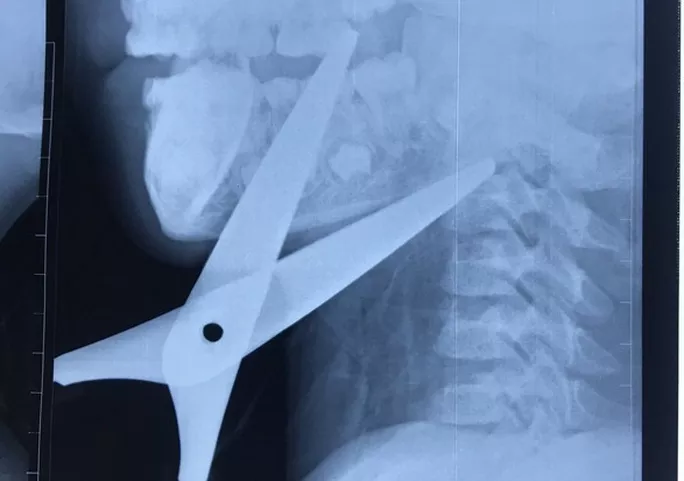

Hình ảnh dị vật qua phim chụp

Hình ảnh phim chụp cho thấy 2 mũi kéo đi theo 2 hướng khác nhau vào vùng góc hàm sàn miệng và đi xuyên qua hệ thống mạch máu, thần kinh, dừng lại khi cắm vào thân đốt sống cổ C2. Lưỡi kéo chạy sau nằm sát động mạch cảnh trong bên phải.